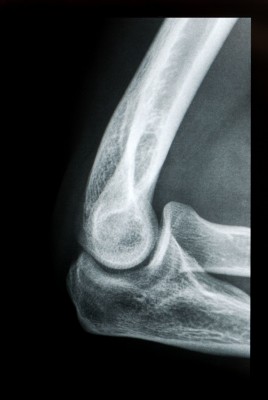

Elbow Dysplasia

The elbow joint joins the humerus, the upper arm bone, to the radius and ulna. All of these bone ends are covered with a smooth form of cartilage that lets the bones glide easily on each other, so the dog can flex and extend his elbow like a well-made hinge. As the joint develops problems in the cartilage or bone arise, this means the joint is unable to articulate or move normally. A knock on effect of elbow dysplasia is secondary osteoarthritis as the joint is unable to move normally wear and tear on the joint starts to occur early on. In some forms of elbow dysplasia the cartilage is forced to wear away causing the dog pain and discomfort which usually manifests as lameness. Elbow dysplasia is more painful and restricting than hip dysplasia and is usually bilateral (in both elbows). There are also usually arthritic changes.